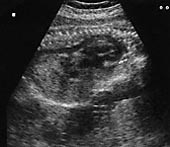

Blodtrykket ved innkomst var 140/90 mm Hg, urinen gav svakt utslag på protein (dipstiks 1+), hemoglobinverdien var 10,5 g/ 100 ml, MCV 73 fl (referanseområde 80 – 99 fl), trombocytter 252 × 109/l (referanseområde 150 – 450 × 109/l), CRP< 10 mg/l (referanseområde< 10 mg/l), ASAT 129 U/l (referanseområde 10 – 35 U/l), ALAT 151 U/l (referanseområde 10 – 35 U/l), LD 775 U/l (referanseområde< 425 U/l), kreatinin 81 µ mol/l (referanseområde 60 – 125  µ mol/l) og urinsyre 440  µ mol/l (referanseområde 120 – 480  µ mol/l). Ultralydundersøkelse viste ascites og ødem hos fosteret (fig 1). Hjertet var forstørret, det var lite fostervann og placenta var stor.